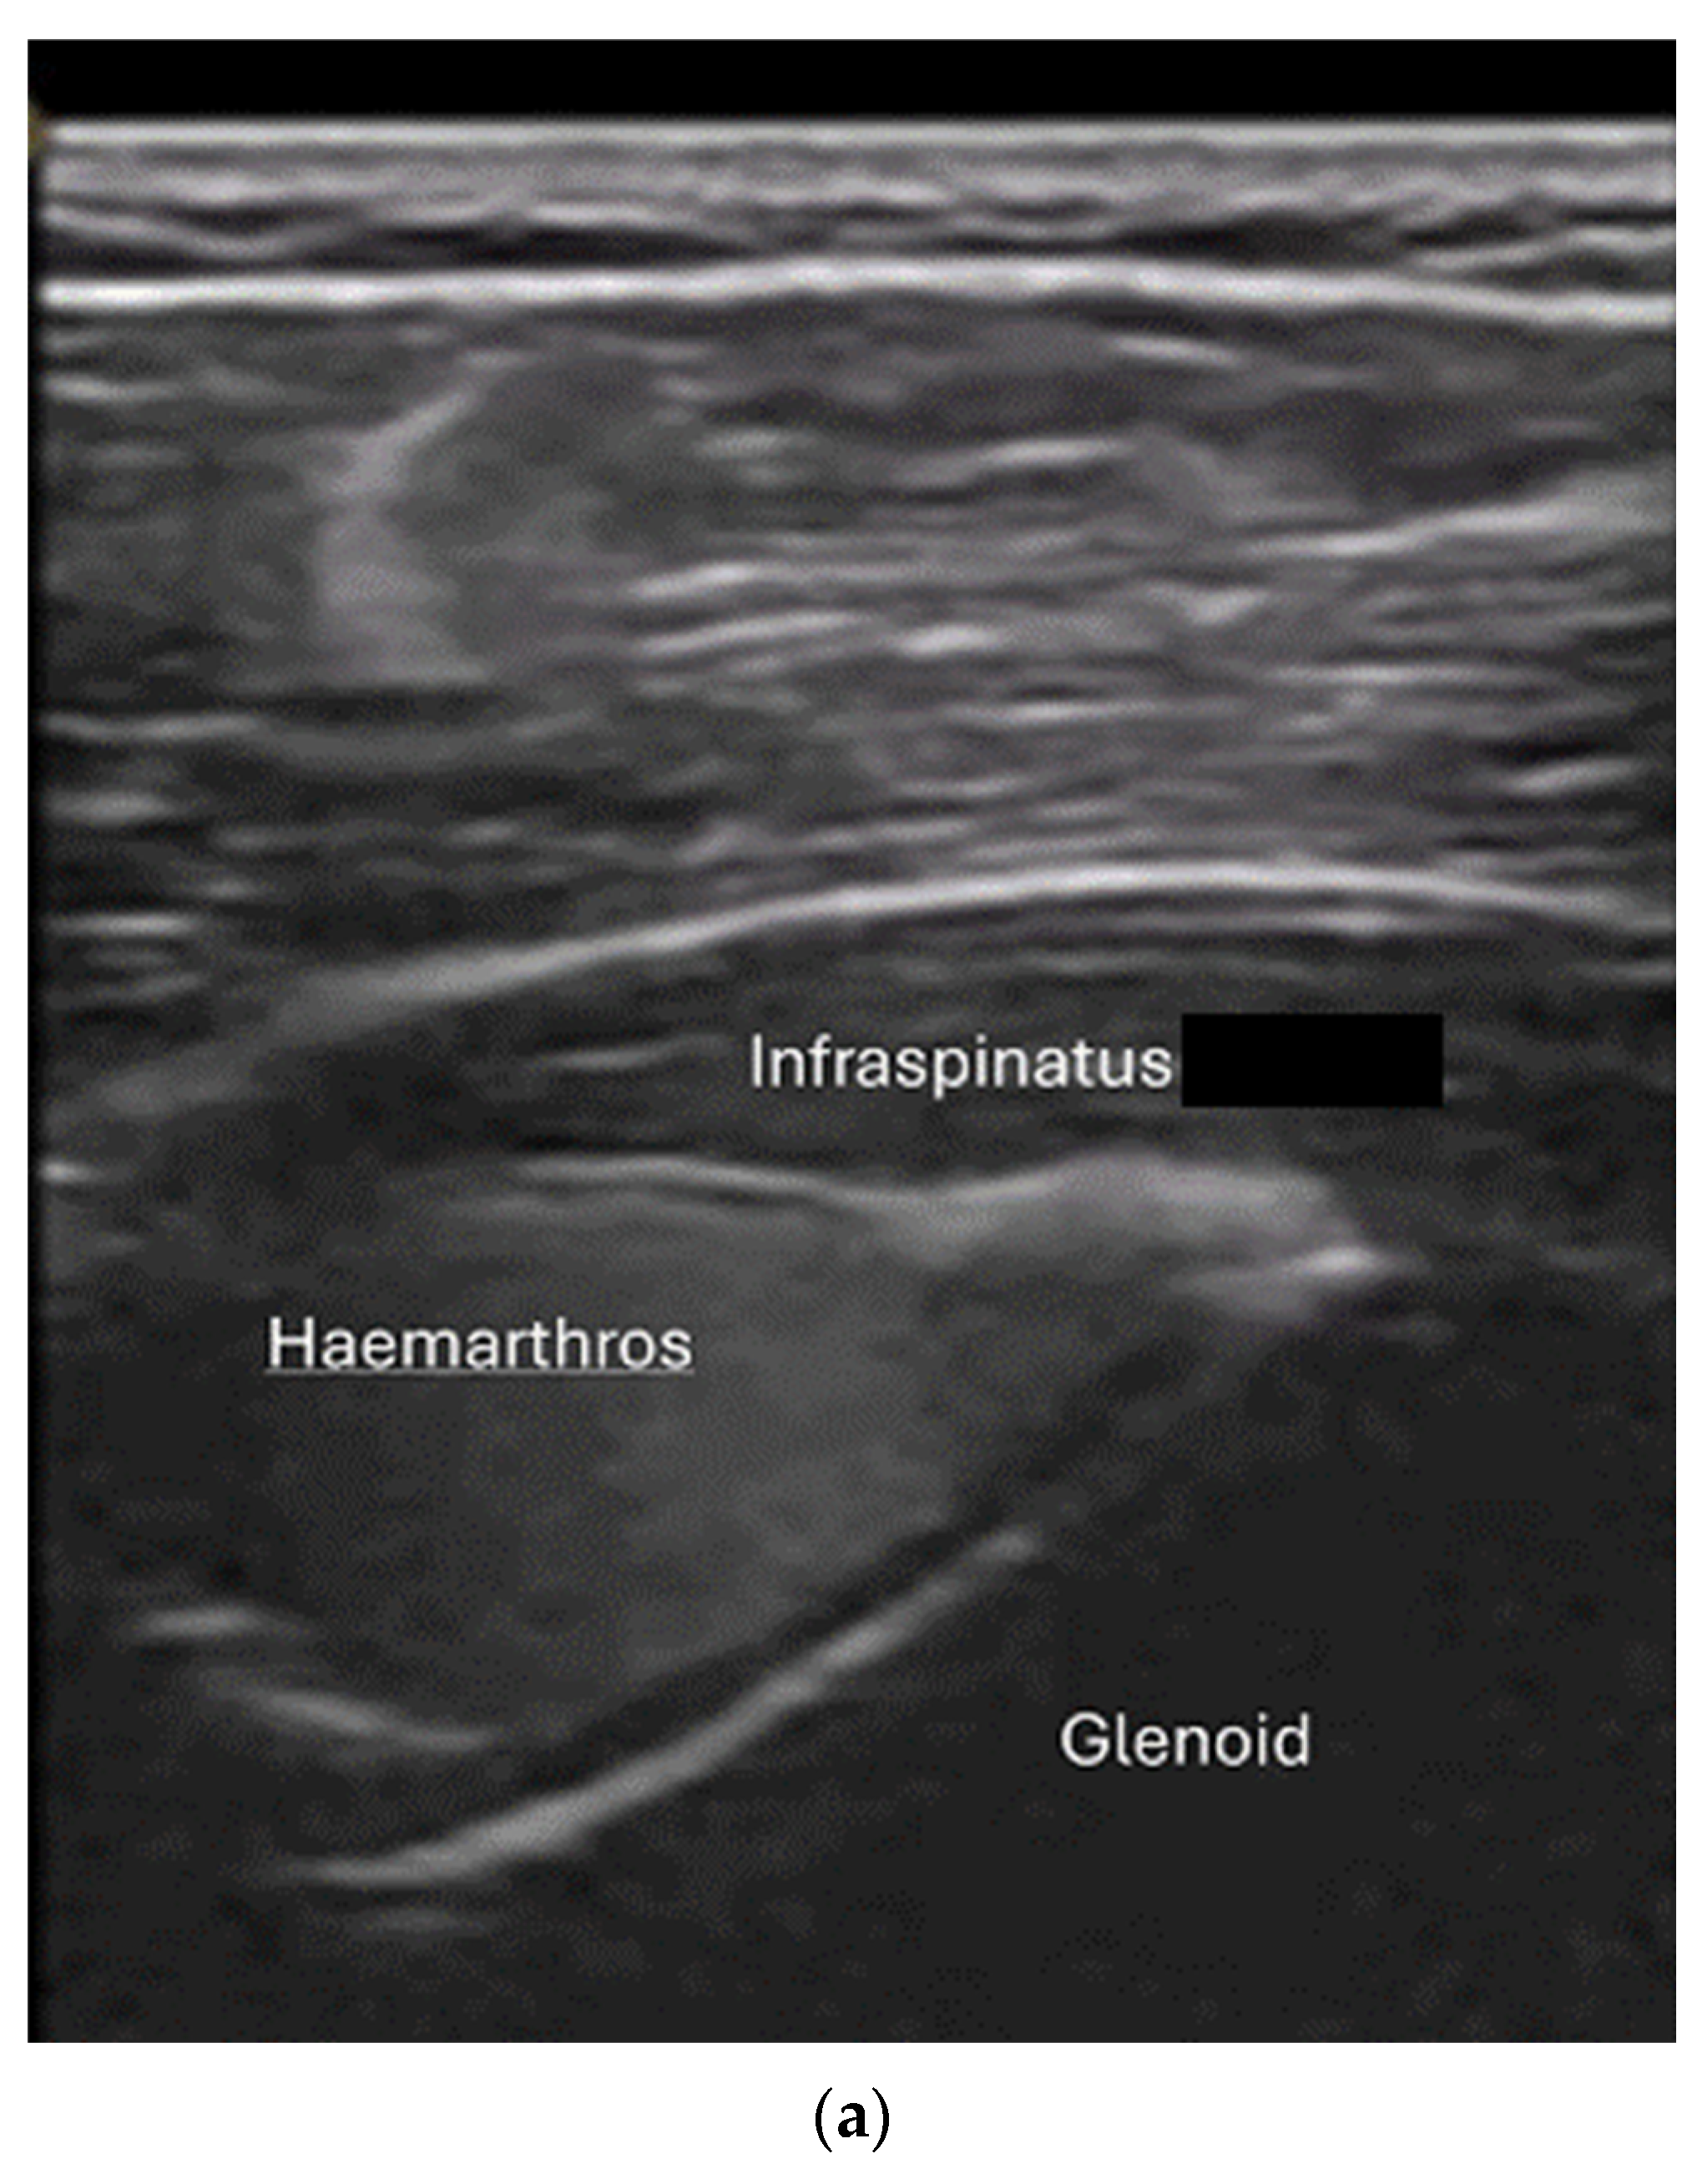

- Joint effusion and liphemarthrosis: fluid accumulation within a joint, sometimes containing fat droplets, which often indicates an intra-articular fracture.

- Example: Suspected left shoulder dislocation